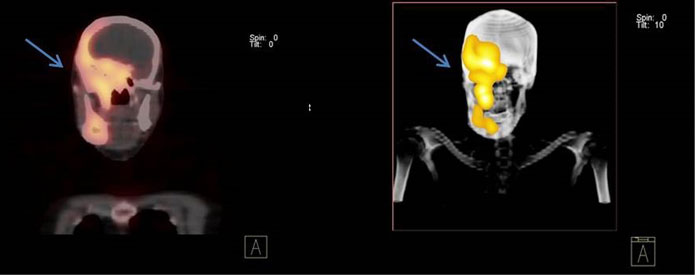

На ОФЭКТ-изображениях участки гиперфиксации РФП в проекции правой половины костей черепа совпадали с зонами литической деструкции при КТ, имели крупно- и мелкоячеистую, трабекулярную структуру с чёткими склеротическими контурами, с отсутствием достоверной визуализации кортикальной кости в данных отделах, выраженного «вздутия» тела нижней челюсти справа, с наличием в данной области участков компактного уплотнения костной ткани (рис. 1, 2). Патологического накопления РФП в других отделах костей скелета выявлено не было.

Рис. 1. Пациент Р. Однофотонная эмиссионная компьютерная томография, совмещённая с рентгеновской компьютерной томографией, костей черепа

Рис. 2. Пациент Р. Трёхмерная компьютерная томография костей черепа